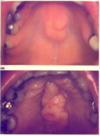

sx of herpangina

fever, sore throat, rash/ulcers on palate –> small vesicles with erythematous base that become ulcers -pain can be severe